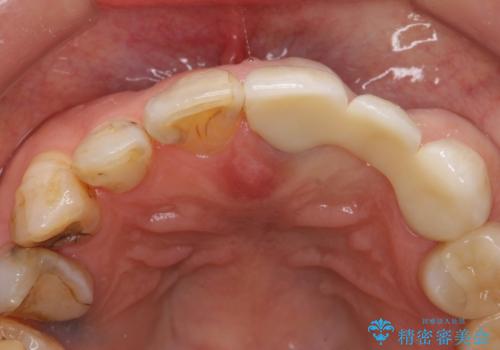

左上2抜歯後、骨および歯肉の回復を待ち、オールセラミッククラウンのブリッジによる欠損補綴を行いました。

- オールセラミッククラウン(sp)…¥130,000×3、仮歯…¥10,000×3、ファイバーコア…¥20,000費用は治療当時の料金となります

前歯の補綴ではオールセラミッククラウンを希望される患者様が多いですが、オールセラミッククラウンの中でも、エコノミー、スタンダード、スペシャル、エクセレントとランクがあります。

その中でも特に審美性が高いのがスペシャル、エクセレントです。スペシャル、エクセレントは口腔内写真をもとに熟練の技工士が、患者様の口腔内に合わせたオーダーメイドのクラウンを製作致します。